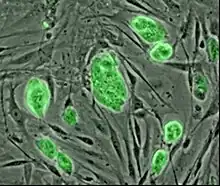

Stamceller er ikke-specialiserede celler som findes i alle flercellede organismer. Stamceller har to egenskaber som udmærker dem i forhold til andre celletyper. Dels kan stamceller gennemgå et ubegrænset antal celledelinger (mitoser), og dels har stamceller evnen til at modnes (differentiere) til flere celletyper. Forskningen omkring menneskelige stamceller blev grundlagt i 1960'erne. Eftersom stamceller har potentiale til at kunne blive til specialiserede celletyper, er der store forhåbninger til deres medicinske rolle.

Nogle stamceller er multipotente; det betyder at de kan dele sig og blive til forskellige specialiserede celler inden for en bestemt gruppe, for eksempel blodceller. Andre stamceller er totipotente; de kan udvikle sig til samtlige celletyper i kroppen.